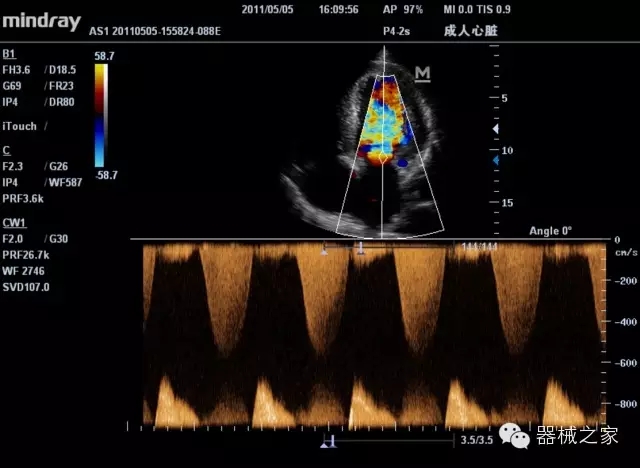

經(jīng)典產(chǎn)品:M7(星鉆)

臨床圖片賞析

產(chǎn)品特點

·裝載有采用Multi-Core多核處理的非嵌入式平臺,成像效率大大提高,并且能夠給用戶帶來高速、多任務(wù)并行信號處理體驗;

·優(yōu)秀的圖像效果、強大的功能體驗、豐富的探頭選擇、合理的便攜式設(shè)計,全中文顯示及病人管理界面,使得M7在任何場合、任何時候都能快速響應(yīng)更好的心血管、腹部、婦產(chǎn)、小器官等常規(guī)超聲檢查以及肌骨、神經(jīng)、顱腦、術(shù)中等新興領(lǐng)域的使用需求;

8倍波束并行處理系統(tǒng)

·在便攜式緊湊平臺上采用更多倍波束并行接收信號處理模式,無論二維還是彩色血流圖像狀態(tài)下,擁有更靈敏的回波頻移捕獲能力,大大提高時間分辨率,尤其使得心血管表現(xiàn)更為突出;

PSHI?寬帶頻移諧波技術(shù)

·在普通組織諧波的基礎(chǔ)上,通過精確控制的波束形成器,發(fā)射兩組具有相位偏差反向的信號,并采用并行信號處理,數(shù)字化合成并采樣回波信號,在高靈敏度的濾波器的處理過程中獲取更純凈的諧波信號,使圖像具有更加出眾的細(xì)節(jié)分辨率;

iClear®+iBeam?

·智能化按線復(fù)合多角度獲取聲束的原始信號,配合智能化的斑點噪聲識別及控制處理技術(shù),整體提高組織結(jié)構(gòu)細(xì)節(jié)分辨率,任何時候都能快速響應(yīng),更好的滿足心血管的使用需求;

支持全新3T工藝探頭群

·包括探頭材料、結(jié)構(gòu)設(shè)計、加工工藝三方面的革新技術(shù)給圖像帶來品質(zhì)的飛躍;

CFDA注冊證編號

·粵食藥監(jiān)械(準(zhǔn))字20132230475